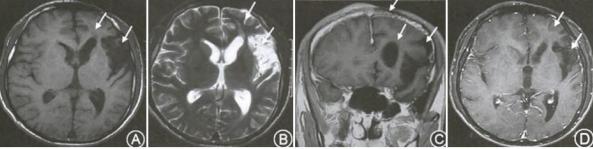

刀砍样线状硬皮病

刀砍样线状硬皮病是局限性硬皮病中较为罕见的一类亚型,除皮肤改变外还可累及皮下组织、肌肉、骨骼和神经系统。

多于儿童期起病,女性为主,进展缓慢。

特征性表现为一侧额面部的条状瘢痕样皮损,多局限于眉弓以上且靠近面部中线,常伴有色素沉着或脱失,部分患者可有脱发。神经系统受累症状最常见为癫痫发作,也可有头痛、视觉改变及精神症状等。

颅脑MRI表现:皮损侧颅内钙化、皮质及皮质下白质高信号病灶、萎缩及灰白质间界限不清。